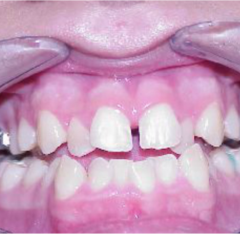

Topic: Expansion

• We are discussing expansion. I am sure, we all have done few. We will revisit protocol.

• Narrow maxilla is indicative of expansion in presense of a crossbite however, expansion is being used as a corrective treatment in Class II and Class III cases as well. We will examine latest literature on the subject.